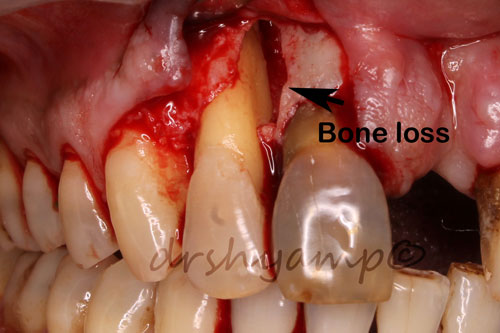

Periodontal flap surgery with bone grafting

Periodontal flap surgery with bone grafting

Periodontal flap surgery with bone grafting

Periodontal flap surgery with bone grafting

Periodontal flap surgery with bone grafting

Periodontal flap surgery with bone grafting

Periodontal flap surgery with bone grafting

Periodontal flap surgery with bone grafting

Periodontal flap surgery with bone grafting

Periodontal flap surgery with bone grafting

Periodontal flap surgery with bone grafting

Periodontal flap surgery with bone grafting

Periodontal flap surgery with bone grafting